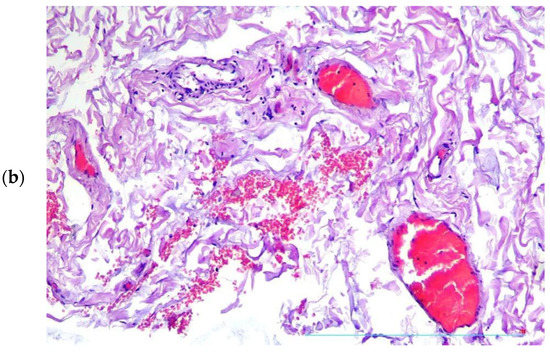

2. Case Presentation